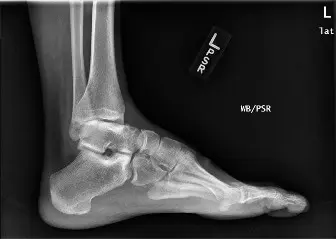

الأشعة السينية (Plain Radiographs)

هي الخطوة الأولى في التشخيص، وتُجرى في قسم الطوارئ. تُظهر الأشعة السينية (الأمامية الخلفية، الجانبية، والخاصة بالمفصل) ما يلي:

*

كسر داخل المفصل:

في الجزء السفلي من قصبة الساق.

تفتت شديد:

للعظم في منطقة السقف الظنبوبي.

انخفاض في السطح المفصلي:

حيث يكون السقف الظنبوبي قد هبط.

كسر مصاحب في الشظية:

غالبًا ما يحدث كسر في الشظية على بعد حوالي 5 سم من مفصل الكاحل.

خلع جزئي في العظم الكاحلي:

قد ينزاح العظم الكاحلي من مكانه الطبيعي.

اتساع في مفصل الكاحل (Mortise Widening):

يشير إلى تمزق في الأربطة التي تربط قصبة الساق والشظية (Syndesmosis).

الشكل 1: صورة أشعة سينية أمامية خلفية أولية توضح كسرًا شديد التفتت داخل المفصل في قصبة الساق السفلية (كسر بيلون) مع انخفاض كبير في السطح المفصلي وخلع جزئي في العظم الكاحلي.